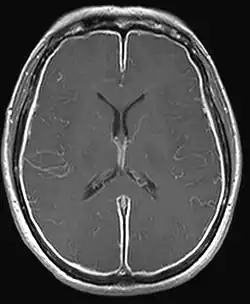

T1W MRI of the brain demonstrating leptomeningeal enhancement consistent with meningitis